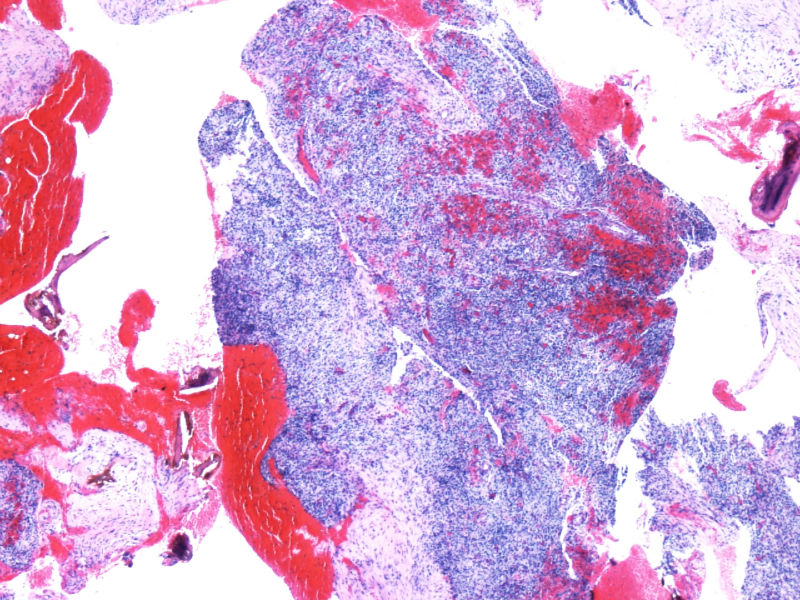

淋巴瘤确实是个麻烦的东西,我前阵子碰到一个CD79a表达阳性的T淋巴母,半个月不到又碰到一个更麻烦的病例,患者颈部淋巴结肿大两年余,近2个月全身淋巴结肿大,免疫组化和形态学看是一个典型的弥漫大B细胞淋巴瘤,但是发现有部分散在细胞CD30阳性,细胞像R-S样,那些R-S样细胞CD15阴性,PAX-5阳性,oct-2和bob-1阴性。

弥漫大B细胞淋巴瘤这样的病例也有啊,如果是老年人,这样的病例可以做EBER,看看是不是EBV阳性的老人年大B,这样的病例常出现R-S样细胞。当然富于H/T的大B也可以。当然grey zone 淋巴瘤也可以。

本例全B,全T缺失,使诊断很困难,淋巴瘤范围内一般考虑①HL;②浆细胞分化的肿瘤如浆细胞骨髓瘤或浆母细胞瘤;③ALCL. 以下为鉴别:

此病例是非常特殊,其表现为:

1)ALCL很少原发于骨组织,

2)肿瘤细胞免疫表型特殊, CD30+CD15+ALK-1+CD43+Perforin+, 而其他PanB细胞和PanT细胞的标记均为阴性。

3)楼主诊断ALCL主要根据是 ALK-1+, 很有说服力!